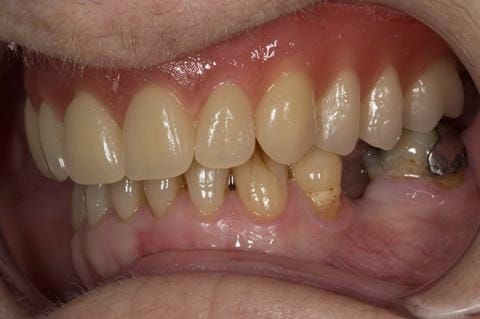

- Eight mandibular anterior teeth worn incisal edges from now extracted maxillary anterior crowns. Gingivitis - owing to inadequate oral hygiene.

- LL6 with large amalgam restoration - healthy periodontium.

- Bruxism.

Following consultation and second discussion appointment the patient chose to have option 2 namely, a window denture - maxillary cobalt chromium based partial denture. The clinical situation and treatment process is shown in detail below with photographs. The patient was successfully rehabilitated with this and her quality of life considerably improved. The clinical work was provided by Finlay and the technical work by Rowan.